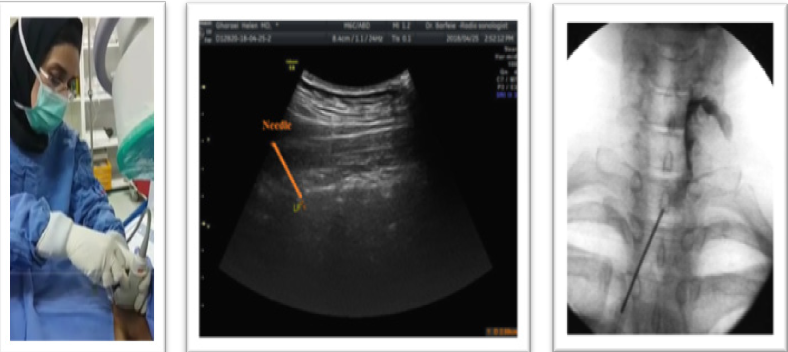

Put the probe at the midline longitudinally to have a sagittal view of the hyperechoic spinous process. Move it a little farther at the paramedian line with heel in maneuver to see the space between the hyperechoic lamina as a hypoechoic acoustic window through which the neuraxial content are visible. The acoustic window between the lamina provides an easy way to spinal and epidural injections. The angle of insonation that produces the best ultrasound visualization of the neuraxial structures or the posterior complex (PC) closely mirrors the angle or trajectory for needle insertion.24−26 Epidural injection performs in prone position but it is possible at lateral or semi lateral position depends on patient comfort. Lumbar and thoracic epidural injection could perform at any level but epidural injection is safer to perform under L2 and thoracic region injection in T4-T6 is more hazardous due to less blood supply. Cervical epidural injection performs in prone position while patient head is hyperextend. It is more difficult than lumbar or thoracic region and best achieve at C7-T1 space by long -axis view of paramedian line with sagittal scanning of the acoustic window. Acoustic window is clearer near to midline, so doesn’t move probe more laterally and use hill- in maneuver and tilt the ultrasound probe slightly medially near to midline not over spinous process to see acoustic window more clearly. By viewing the acoustic window, you can easily insert the needle under the probe with in-plan technique and direct it to the window. The pop sensation in the blind method will also spark you, though in the cervical injection is not very helpful. Benefit the fluoroscopy view and confirm the correct location by injecting the contrast material for patient safety (Figure 8) (Figure 9).

Ultrasound guided medial branch block

After identification of the midline and paramedian view, take the probe more laterally and move away from the lamina to see the articular process that present as a continuously wavy hyperechoic line without an intervening gap. Z joint sono-anatomy view on the axial and sagittal plane is the key landmark for the medial branch block and periradicular injection. Scan the Z joint in the axial view. Then enter the needle in - plane from the outside of the probe and under it down to up (except L5 which is up to down) and toward the space between the TP and the SAP which is really their hyper echoic acoustic shadow in axial view and forward needle till contact the nearby bone. Then turn the probe 90 ° and put it longitudinally at the Z line to ensure that the needle is at the top of the transverse process and not inserted into the IVF. To maintain the patient's safety, help live fluoroscopy to ensure unwanted intravascular or epidural injection (Figure 11).